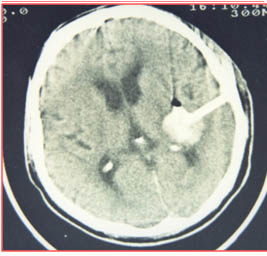

一位市區(qū)的老年男性,高某某,90歲,因高血壓突發(fā)腦出血,導致昏迷,左側肢體偏癱,收住我院急診科治療。入院后,急診科立即進行診查后,考慮到老人年老、體弱,采用常規(guī)開顱手術方法治療創(chuàng)傷大,愈后差,且患者顱內出血部位較深,手術過程重患者顱內再次出血可能性大,經過認真分析、評估患者病情,決定為患者采取腦出血微創(chuàng)治療術,即在患者頭皮上做長約2厘米長傷口,顱骨鉆一1厘米小孔,血腫腔置入軟硅膠管,引流血腫。術前CT定位后,送入手術室,只20分鐘后手術完畢,手術非常成功,及時挽救了患者的生命,術后第2天,患者癱瘓肢體肌力明顯增強,術后第3天患者清醒,15天后可以下床活動,現(xiàn)已痊愈出院。先進、精確的微創(chuàng)手術在我院急診科發(fā)揮著事半功倍的作用。

腦出血術前